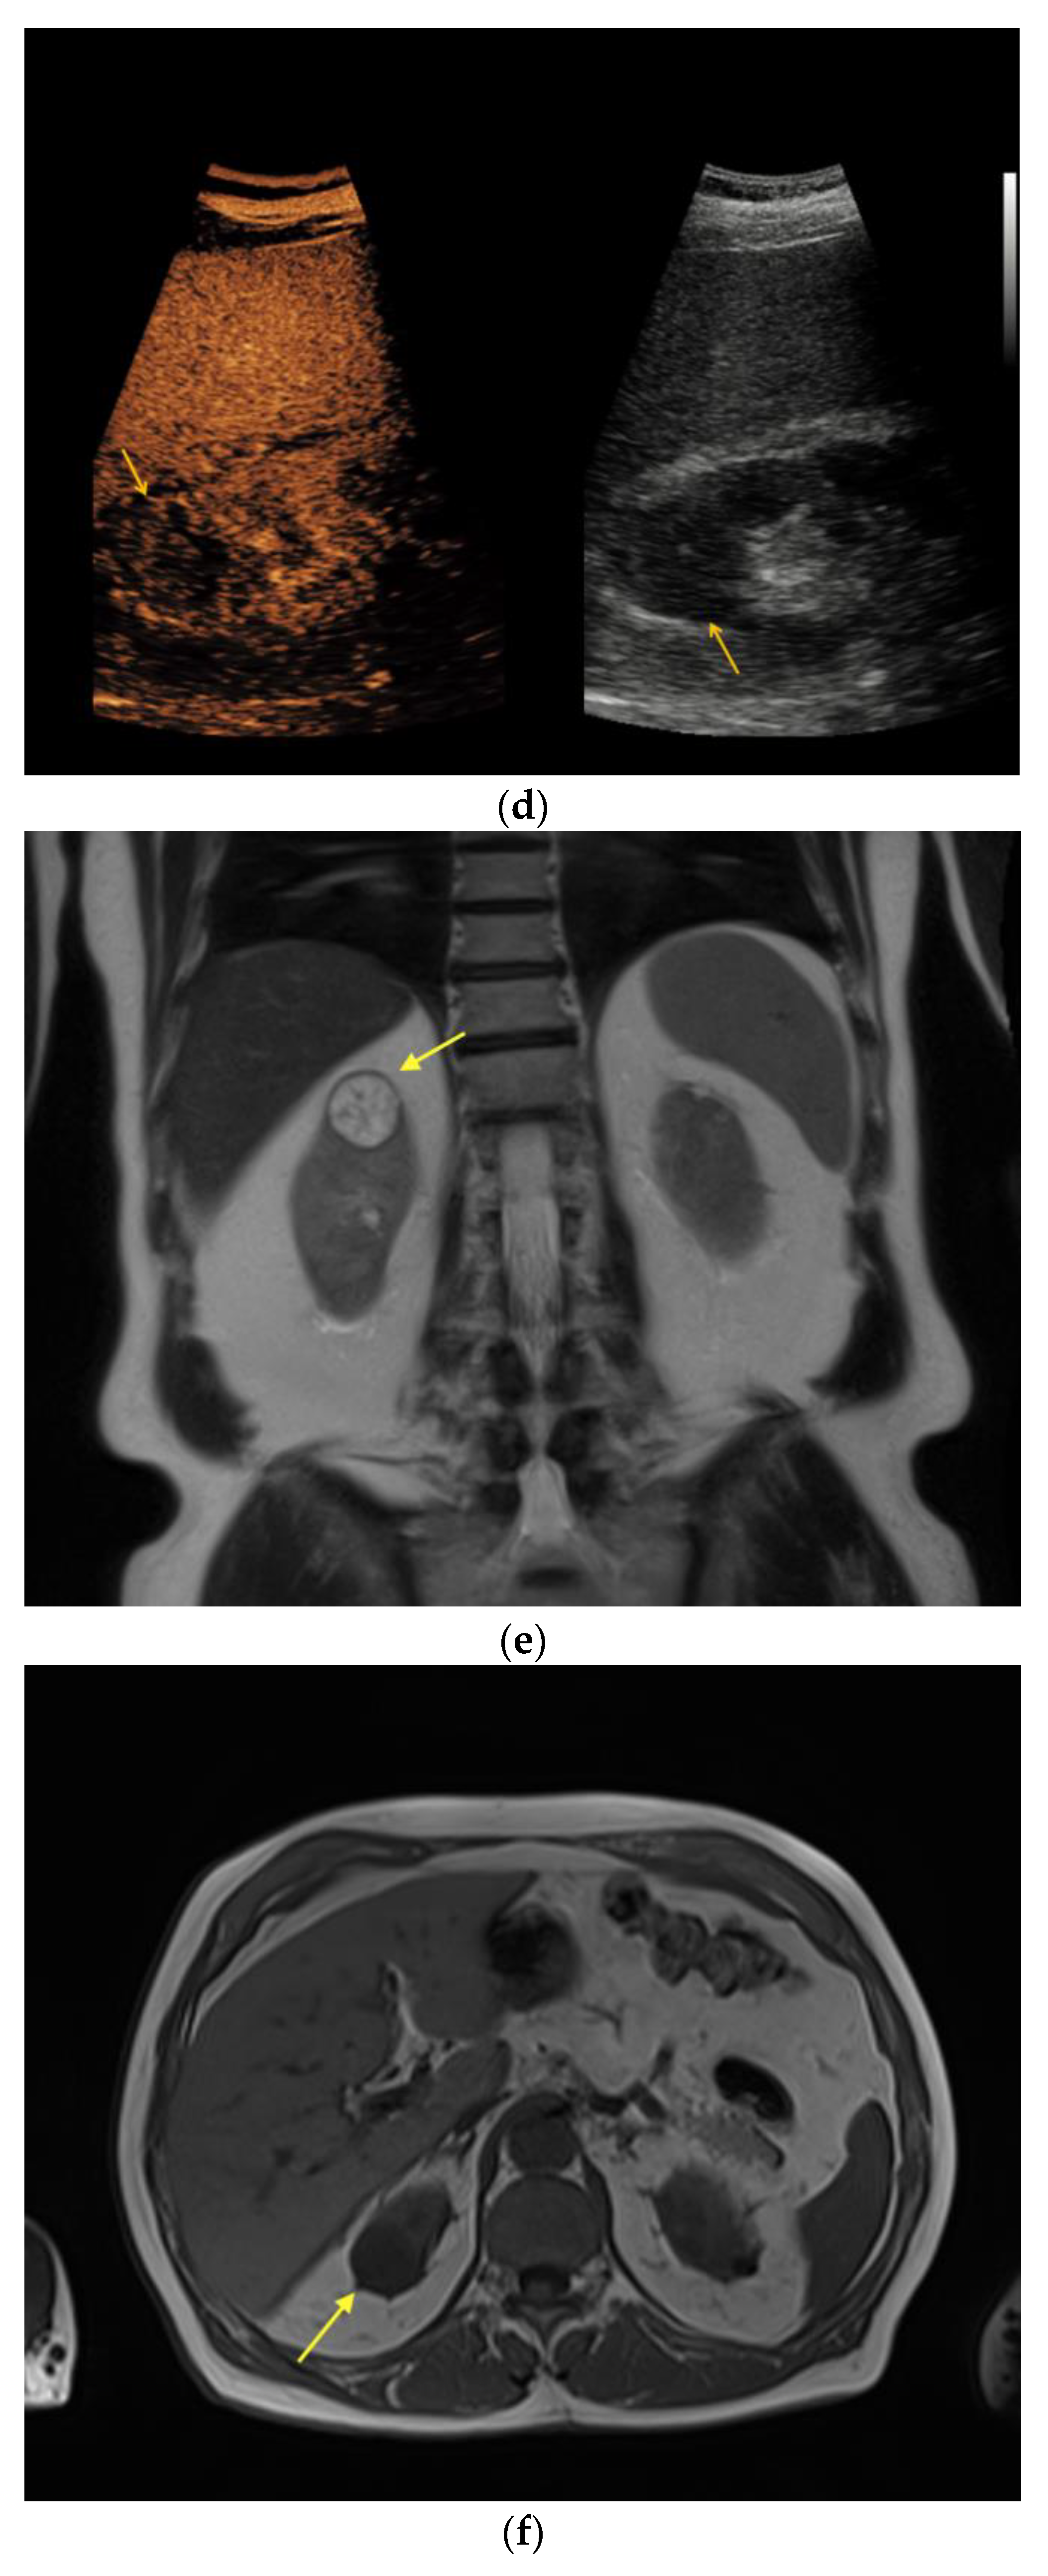

| Patient | Sex | Age | Location | Size (cm) | Native B-Mode | Vascularization (CD) | CEUS | CT | MRI | Treatment: Histopathology |

|---|---|---|---|---|---|---|---|---|---|---|

| #1 | F | 49 | R | 5.6 | Cystic, septated | - | Intraseptal | - | Intraseptal enhancing → Bosniak IIF | Partial nephrectomy: Clear-cell RCC |

| #2 | M | 54 | L | 3.0 | Cystic, hypoechoic areas, wall thickening | - | Peripheral | - | - | Partial nephrectomy: chromophobe RCC |

| #3 | F | 61 | R | 3.5 | Cystic, septated | - | Peripheral, intraseptal | - | - | Partial nephrectomy: clear-cell RCC |

| #4 | F | 43 | R | 1.6 | Cystic | - | Peripheral | - | - | Partial nephrectomy: clear-cell RCC |

| #5 | F | 64 | L | 5.0 | Cystic, focally thickened, septa | - | Intraseptal | - | - | Partial nephrectomy: clear-cell partial cystic RCC |

| #6 | M | 74 | L | 2.0 | Cystic | - | Peripheral, intraseptal | - | - | Partial nephrectomy: clear-cell RCC |

| #7 | F | 66 | L | 7.0 | Cystic, complex | - | Intraseptal | - | - | Partial nephrectomy: multilocular cystic RCC |

| #8 | M | 54 | L | 1.5 | Cystic, wall thickening | - | Intraseptal | - | - | Partial nephrectomy: clear-cell RCC |

| #9 | M | 76 | L | 1.6 | Cystic | - | Peripheral, wash-out | - | - | Partial nephrectomy: papillary RCC |

| #10 | F | 66 | R | 1.5 | Cystic | - | Intraseptal | - | - | Partial nephrectomy: clear-cell RCC |

| #11 | M | 75 | L | 2.7 | Cystic, focally thickened septa | - | Intraseptal | - | - | Partial nephrectomy: Papillary RCC |

| #12 | M | 52 | L | 1.5 | Cystic, focally thickened septa | - | Intraseptal | - | - | Partial nephrectomy: clear-cell RCC |

| #13 | M | 68 | L | 1.5 | Partially cystic | - | Peripheral | - | - | Partial nephrectomy: clear-cell RCC |

| #14 | M | 86 | L | 4.0 | Cystic, septated | - | Intraseptal | Septated, calcified, early enhancement, wash-out in delayed phase → Bosniak III | - | Nephrectomy: cystic clear-cell RCC |

| #15 | M | 63 | R | 2.0 | Cystic | - | Peripheral | - | - | Nephrectomy: clear-cell RCC |

| #16 | F | 62 | L | 2.5 | Partially cystic | - | Peripheral, intraseptal wash-in/wash-out | - | Native MRI: T2w: mainly hyperintense with hypointense septations T1w: hypointense | Renal biopsy: oncocytoma |

| #17 | F | 64 | R | 3.5 | Cystic | - | Intraseptal | - | - | Partial nephrectomy: cystic hamartoma |

| #18 | M | 67 | R | 3.0 | Partially cystic, focally thickened septa | - | Intraseptal | - | - | Partial nephrectomy: cyst, no malignancy |

| #19 | M | 71 | L | 1.2 | Cystic | - | Peripheral | - | - | Partial nephrectomy: cyst, no malignancy |

| #20 | F | 48 | L | 10.0 | Cystic, septated | - | Intraseptal | - | - | Partial nephrectomy: adult cystic nephroma |

| #21 | M | 76 | R | 2.0 | Cystic | - | Peripheral and Intraseptal wash-in/wash-out | - | - | Partial nephrectomy: oncocytoma |

| #22 | M | 46 | R | 0.8 | Cystic | - | Peripheral wash-in/wash-out | - | - | Partial nephrectomy: papillary adenoma |

| #23 | F | 69 | L | 8.0 | Cystic, septated | - | Intraseptal | - | - | Partial nephrectomy: cyst, no malignancy |

| #24 | M | 69 | R | 2.5 | Cystic | - | Peripheral wash-in/wash-out | - | - | Partial nephrectomy: Papillary RCC |

| #26 | M | 66 | R | 5.0 | Cystic | - | Peripheral | - | - | Partial nephrectomy: Hemorrhagic, xantho-granulomatous cyst, no malignancy |

| #27 | M | 67 | R | 7.0 | Cystic, septated, partially calcified | - | Peripheral, intraseptal | Septated, partially calcified → Bosniak IIF | - | Partial nephrectomy: oncocytoma |

| #32 | M | 83 | L | 4.7 | Cystic | - | Peripheral | - | - | Partial nephrectomy: clear-cell RCC |

| #35 | M | 48 | R | 2.5 | Cystic, septated | - | Intraseptal wash-in/wash-out | - | - | Partial nephrectomy: clear-cell RCC |

| #38 | M | 60 | R | 1.2 | Cystic, septated | - | Peripheral | Septated, contrast-enhanced → Bosniak type IIF | - | Partial nephrectomy: clear-cell RCC |